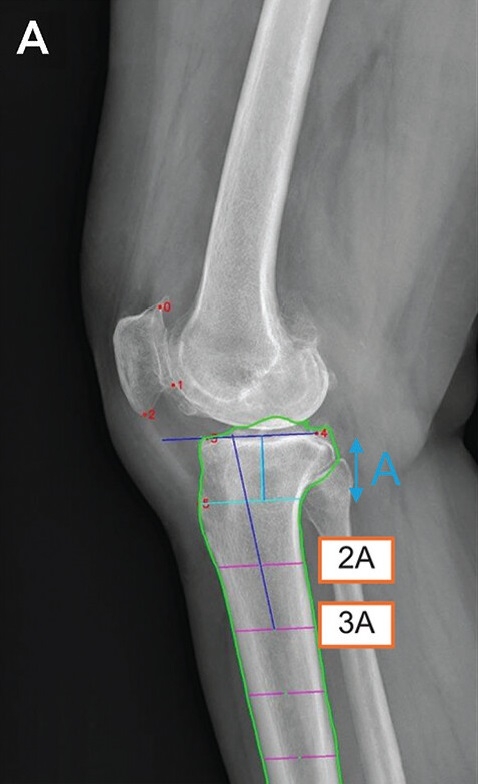

| 딥러닝 모델의 측정 매커니즘. 6개의 해부학적 기준점(빨간 점)을 자동 인식한 후, 경골의 관절선과 중심축(파란 선)을 결정해 경골 후방 기울기를 계산한다. |

이 모델은 무릎뼈의 6개의 해부학적 기준점(랜드마크)을 자동으로 인식한다. 이후 각 기준점을 이용하여 경골의 관절선과 중심축을 결정하고, 이를 바탕으로 기울기를 계산한다. 이 방법은 엑스레이 영상이 짧거나, 실제 거리 측정이 불가능한 경우 등 다양한 임상 조건에서 활용 가능하다는 장점이 있다. 이 모델과 전문의 수기 측정의 성능을 비교한 결과, 딥러닝 모델의 측정 시간이 수기 측정 대비 10배 이상 빨랐다. (평균 2.5초 vs 평균 26.1초)